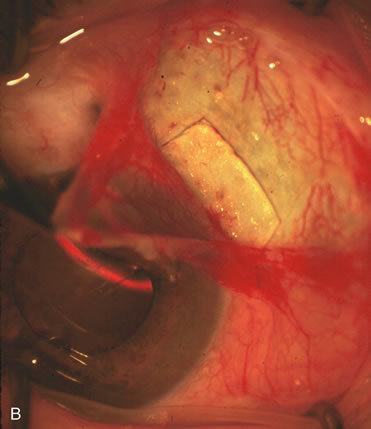

CASE 5: ANTICIPATED LENS EXTRACTION POST SUCCESSFUL TRABECULECTOMY

A patient with long-standing primary open-angle glaucoma with a successful glaucoma filtration procedure and IOP of 10 mm Hg on no antiglaucoma medications develops a significant, moderately dense nuclear sclerotic cataract. This patient is best served by small incision cataract extraction with foldable IOL implantation. Less desirable options include ECCE with IOL implant via clear cornea, temporal limbus, or inferior approach. Astigmatism, wound instability, prolonged visual recovery, visual fluctuation, exposed sutures, and bleb failure are the major drawbacks to large-incision lens extraction. Even after the surgeon has mastered large-incision clear corneal cataract extraction, long-term wound shift and astigmatism are a chronic problem (Fig. 6). Inferior cataract extraction is difficult for those not experienced with it. With the advent of small-incision phacoemulsification surgery, the surgeon is now able to use a limbus approach adjacent to the bleb or a clear corneal temporal approach. Postoperative inflammation is less with the smaller incision, and filtering blebs are more likely to survive. Patients with IOP greater than 10 mm Hg after a filtering procedure are more likely to experience permanent IOP elevation after phacoemulsification. Patients should understand that IOP elevation post cataract extraction is always an issue, even with a functioning filter.

Fig. 6. ECCE following trabeculectomy. The larger corneal incision associated with ECCE leads to a host of problems that are typically less severe with small incision cataract surgery. With improved phacoemulsification techniques, this type of incision is infrequently encountered. This bleb failed following ECCE, and topical antiglaucoma therapy was restarted. Long-term wound drift; astigmatism, and corneal decompensation are additional visual factors. However, when the nucleus is brunescent and phacoemulsification risky, surgeons with the skill to convert to ECCE through a clear corneal incision are at a significant advantage. This 11-mm free hand incision takes considerable practice and skill to master.